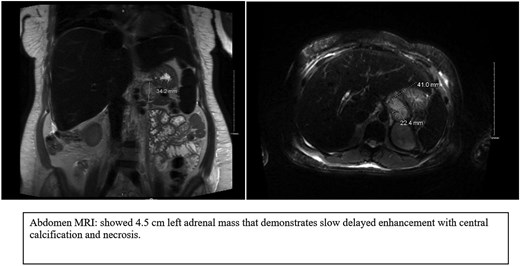

MRI as shown in (Fig. 2), a 2.2 × 4.5 × 3.5 cm well-defined, mostly separable left para-aortic mass from the spleen and pancreas, arising from the left adrenal gland. It is hypointense on T1, heterogeneously hyperintense on T2, with slow enhancement, mild diffusion restriction, central calcification, and necrosis—no invasion into adjacent structures. Differential diagnoses include ganglioneuroma and hemangioma. Further positron emission tomography (PET/CT) is recommended to confirm benignity and rule out adrenocortical carcinoma.

MRI images showed a well-defined left para-aortic mass that mostly arises from the left adrenal gland.